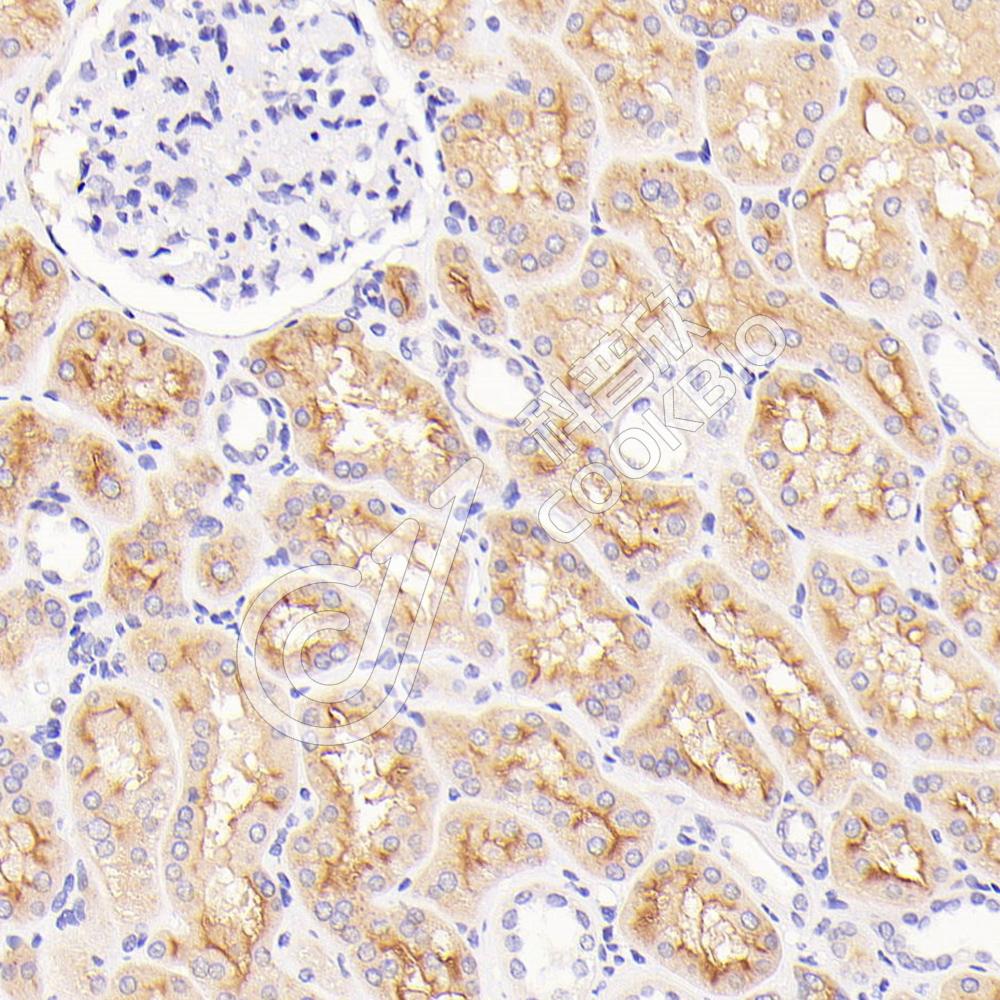

IHC检测CD3蛋白(货号 K1334011).

样品: 大鼠脾, 4%多聚甲醛 (货号KSG1101) 固定12-24小时.

抗原修复: 柠檬酸抗原修复液(干粉, pH 6.0) (KSG1201), 高压锅均匀喷气计时2分钟.

—抗: 1: 1100稀释, 4℃ 孵育过夜.

二抗: S-vision免疫组化多聚二抗(山羊抗兔),即用型 (货号KB3906), 室温孵育20分钟.